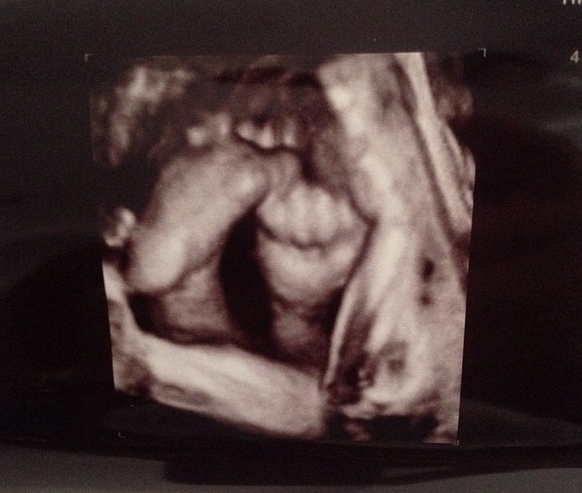

Insarcinata in sapte luni, Aylin Cadir a facut publica prima poza cu bebelusul ei. Vedeta a postat ecografia copilului pe pagina ei de socializare, iar prietenii virtuali au felicitate-o si i-au dorit o nastere usoara.

Aylin a postat ecografia pe pagina ei de socializare